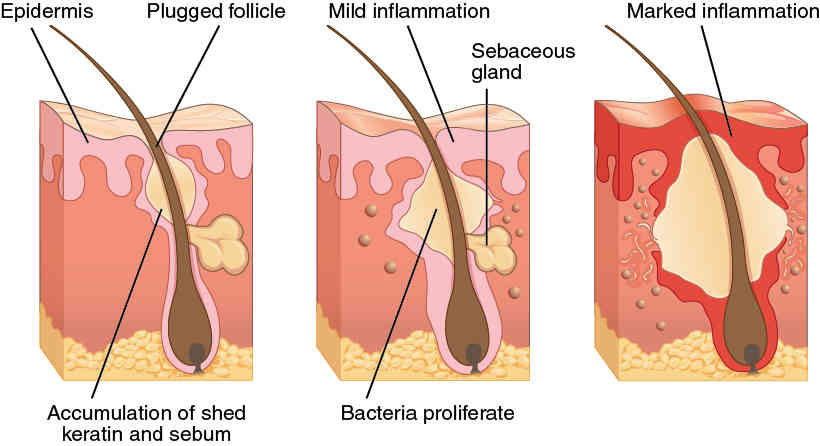

This page is under construction. For now, it is just a resource of the images found in the OpenStax Anatomy and Physiology Handbook. It wil slowly change into a revision tool. Each slide has a number. Use this to refer to the slide. When completed, it will have an unlabelled section, with labelled slides in parallel. On the unlabelled slides, write your answer and use the labelled slide to assess yourself. Keep track by also noting the number on each slide. Improvement at each attempt is important, more so than full marks on a first attempt.